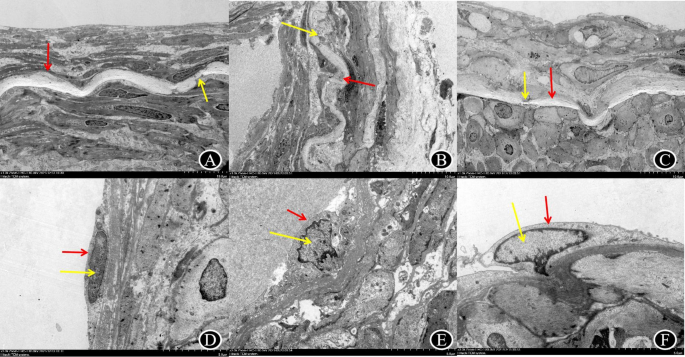

The score of IEL rupture on the brain surface was assessed for hemorrhagic MMD at Suzuki stages II(0.00), Suzuki stage III ([M(Q1,Q3) = 2.00(1.25,2.75)]), Suzuki stage IV ([M(Q1,Q3) = 2.00(1.00,3.00)]), and Suzuki stage V ([M(Q1,Q3) = 1.50(1.00,2.00)]), showing no statistically significant difference (P = 0.293).(Table 9, Fig. 5).

Table 9 Comparative analysis of the endothelial cell area and Internal Elastic Iamina break of the brain surface vessels in different Suzuki stages of hemorrhagic moyamoya disease. Fig. 5 A–D vascular endothelial cells of hemorrhagic MMD (red arrow) are long spindle shape, complete cell membrane, irregular nucleus (yellow arrow), heterochromatin border.With the Suzuki stage, endothelial cells became pyknosis and necrosis increased; E–H the internal elastic lamina (red arrow) in hemorrhagic MMD was wavy, and the thinning and fracture (yellow arrow) worsened with the progression of Suzuki stage.(A and E:Suzuki II stage; B and F:Suzuki III stage; C and G:Suzuki IV stage; D and H: Suzuki V stage ).

(2)

The area of vascular endothelial cells on the brain surface was evaluated for hemorrhagic MMD at Suzuki stage II (19.22 μm2), Suzuki III ([M(Q1,Q3) = 13.84(2.76,18.1) μm2]), Suzuki IV ([M(Q1,Q3) = 15.23(6.23,22.89) μm2]), and Suzuki V ([M(Q1,Q3) = 1.039(0.00,7.025) μm2]), showing no statistically significant difference (P = 0.235). However, compared to Suzuki stages II-IV, the endothelial cell area in phase V showed significant reduction (Table 9, Fig. 5).

The score of IEL rupture for ischemic MMD at Suzuki stage II ([M(Q1,Q3) = 0.50(0.00,3.00)]), Suzuki stage III ([M(Q1,Q3) = 1.00(0.00,1.00)]), Suzuki stage IV ([M(Q1,Q3) = 1.00(0.75,2.00)]), and stage V ([M(Q1,Q3) = 1.00(1.00,1.00)]), showed no statistically significant difference (P = 0.886).(Table 11, Fig. 6).

Table 11 Comparative analysis of the endothelial cell area and Internal Elastic Iamina break of the brain surface vessels in different Suzuki stages of ischemic moyamoya disease. Fig. 6 A–D vascular endothelial cells of ischemic MMD (red arrow) are long spindle shape, complete cell membrane, irregular nucleus (yellow arrow), heterochromatin border.There was no significant difference in the different Suzuki stages ; E–H the internal elastic lamina (red arrow) in ischemic MMD was wavy, with local thin fracture (yellow arrow) and no obvious difference under different Suzuki stages.(A and E:Suzuki II stage; B and F:Suzuki III stage; C and G:Suzuki IV stage; D and H: Suzuki V stage ).

The area of vascular endothelial cells for ischemic MMD at Suzuki stages II ([M(Q1,Q3) = 16.68(6.01,27.44) μm2]), III ([M(Q1,Q3) = 16.45(11.19,24.23) μm2]), IV ([M(Q1,Q3) = 15.19(10.20,23.96) μm2]), and V ([M(Q1,Q3) = 18.36(17.99,18.74) μm2]), showed no statistically significant difference (P = 0.957).(Tables 11, 12, and 13 Fig. 6).